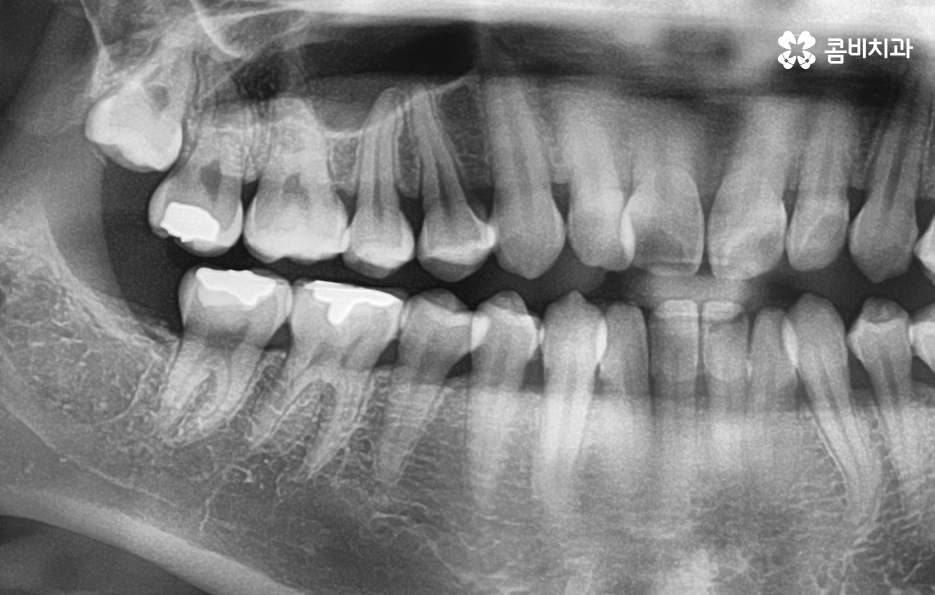

현대인들의 경우 사랑니가 4개 모두 나기 보다는 1~3개 씩 나는 경우도 많고 요즘 젊은 분들은 턱 뼈가 좁은 편인 분들이 많다보니 사랑니가 나올 공간이 부족하여 매복사랑니를 갖고 계신 경우도 많이 있어요

그리고 보편적으로는 윗니의 경우 중력에 의해 사랑니가 똑바로 나오는 경우가 좀더 많다면 아랫니의 경우 누워서 자라는 경우가 좀 더 많이 있는데요. 사랑니는 이처럼 나오는 위치나 방향의 개인차도 크고 정상적으로 똑바로 나온 경우에도 칫솔질이 잘 닿지 않거나 치석이 쌓이기 쉬운 위치이다 보니 결국 발치로 이어지는 경우가 많을 거예요

사랑니의 문제는 육안으로 상태 파악이 어려운 경우가 많기 때문에 주기적인 검진을 하지 않고 통증이나 매복사랑니 냄새와 같은 자각증상을 통해 치과에 방문하시면 치료가 복잡해지는 경우를 종종 볼 수 있는데요

예를 들어 사랑니의 충치가 어금니의 인접면까지 같이 발생한 경우에는 사랑니 발치 만으로 끝나는 것이 아니라 어금니 치료까지 함께 진행되어야 하는 경우도 있고 사랑니로 인한 염증이 심해진 경우에도 잇몸 치료가 발치와 함께 진행되어야 하는 경우도 있을 거예요

매복사랑니의 경우 당장 발치가 필요하지 않은 경우에도 주기적으로 치과 검진을 통해 사랑니의 상태를 체크할 필요가 있으며 특히 어금니 뿌리 쪽에 안좋은 영향을 주고 있거나 우려가 있다면 발치 계획을 세워야 할 거예요